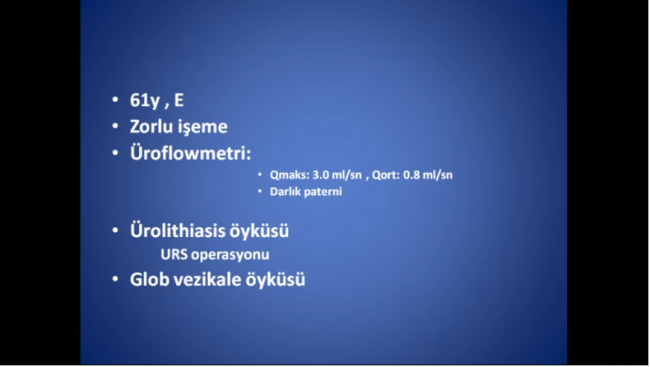

Notice: Trying to access array offset on value of type null in /home/u9176434/en.uretradarligi.com/wp-content/plugins/js_composer/include/autoload/vc-shortcode-autoloader.php on line 64 Notice: Trying to access array offset on value of type null in /home/u9176434/en.uretradarligi.com/wp-content/plugins/js_composer/include/autoload/vc-shortcode-autoloader.php on line 64 Notice: Trying to access array offset on value of type null in /home/u9176434/en.uretradarligi.com/wp-content/plugins/js_composer/include/autoload/vc-shortcode-autoloader.php on line 64 Ventral buccal mucosal urethroplasty ÖZGEÇMİŞ Yaş: 64…